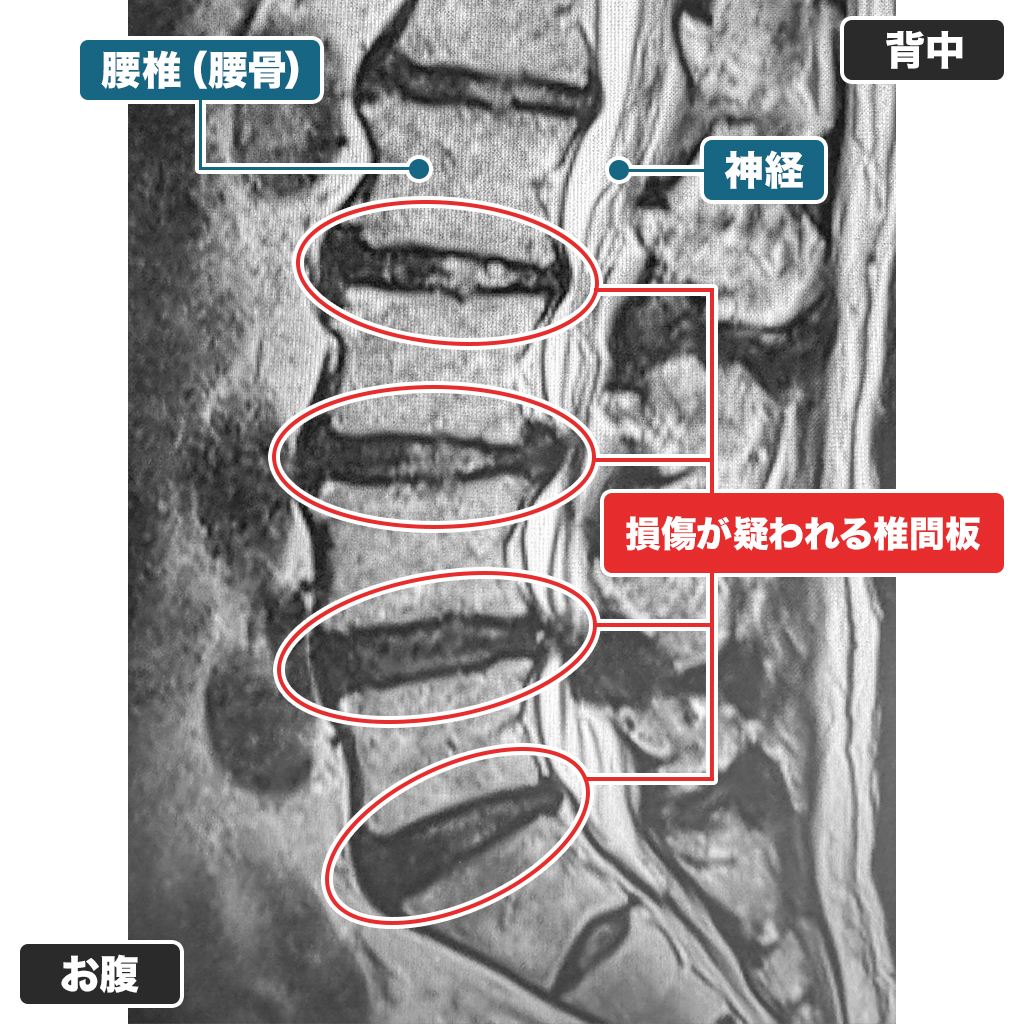

MRI検査

腰のMRI検査です。複数箇所で椎間板容量が低下しており、脊柱管狭窄症も認めます。